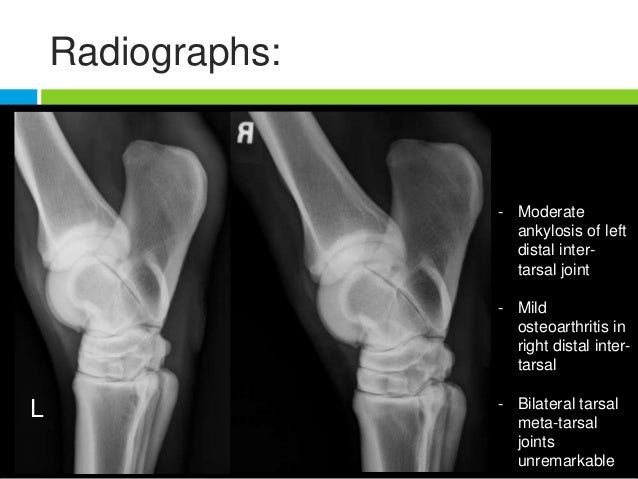

tarsal ankylosis radiographs shockwave distal osteoarthritis

Bone or muscle???. Bone muscle binary octet stream. Tarsal ankylosis radiographs shockwave distal osteoarthritis